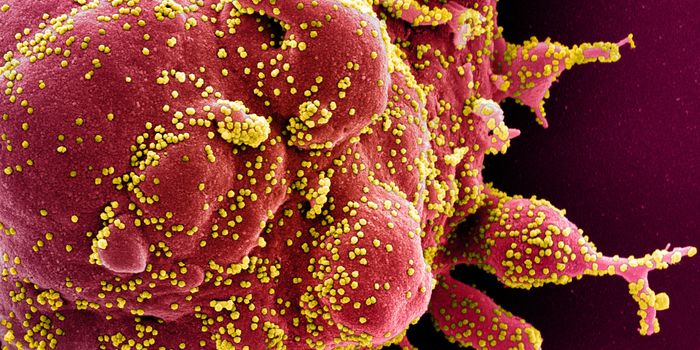

MAY 10, 2021MicrobiologyThe pandemic virus SARS-CoV-2 has changed the world in devastating ways, taking hundreds of thousands of lives & new var ...